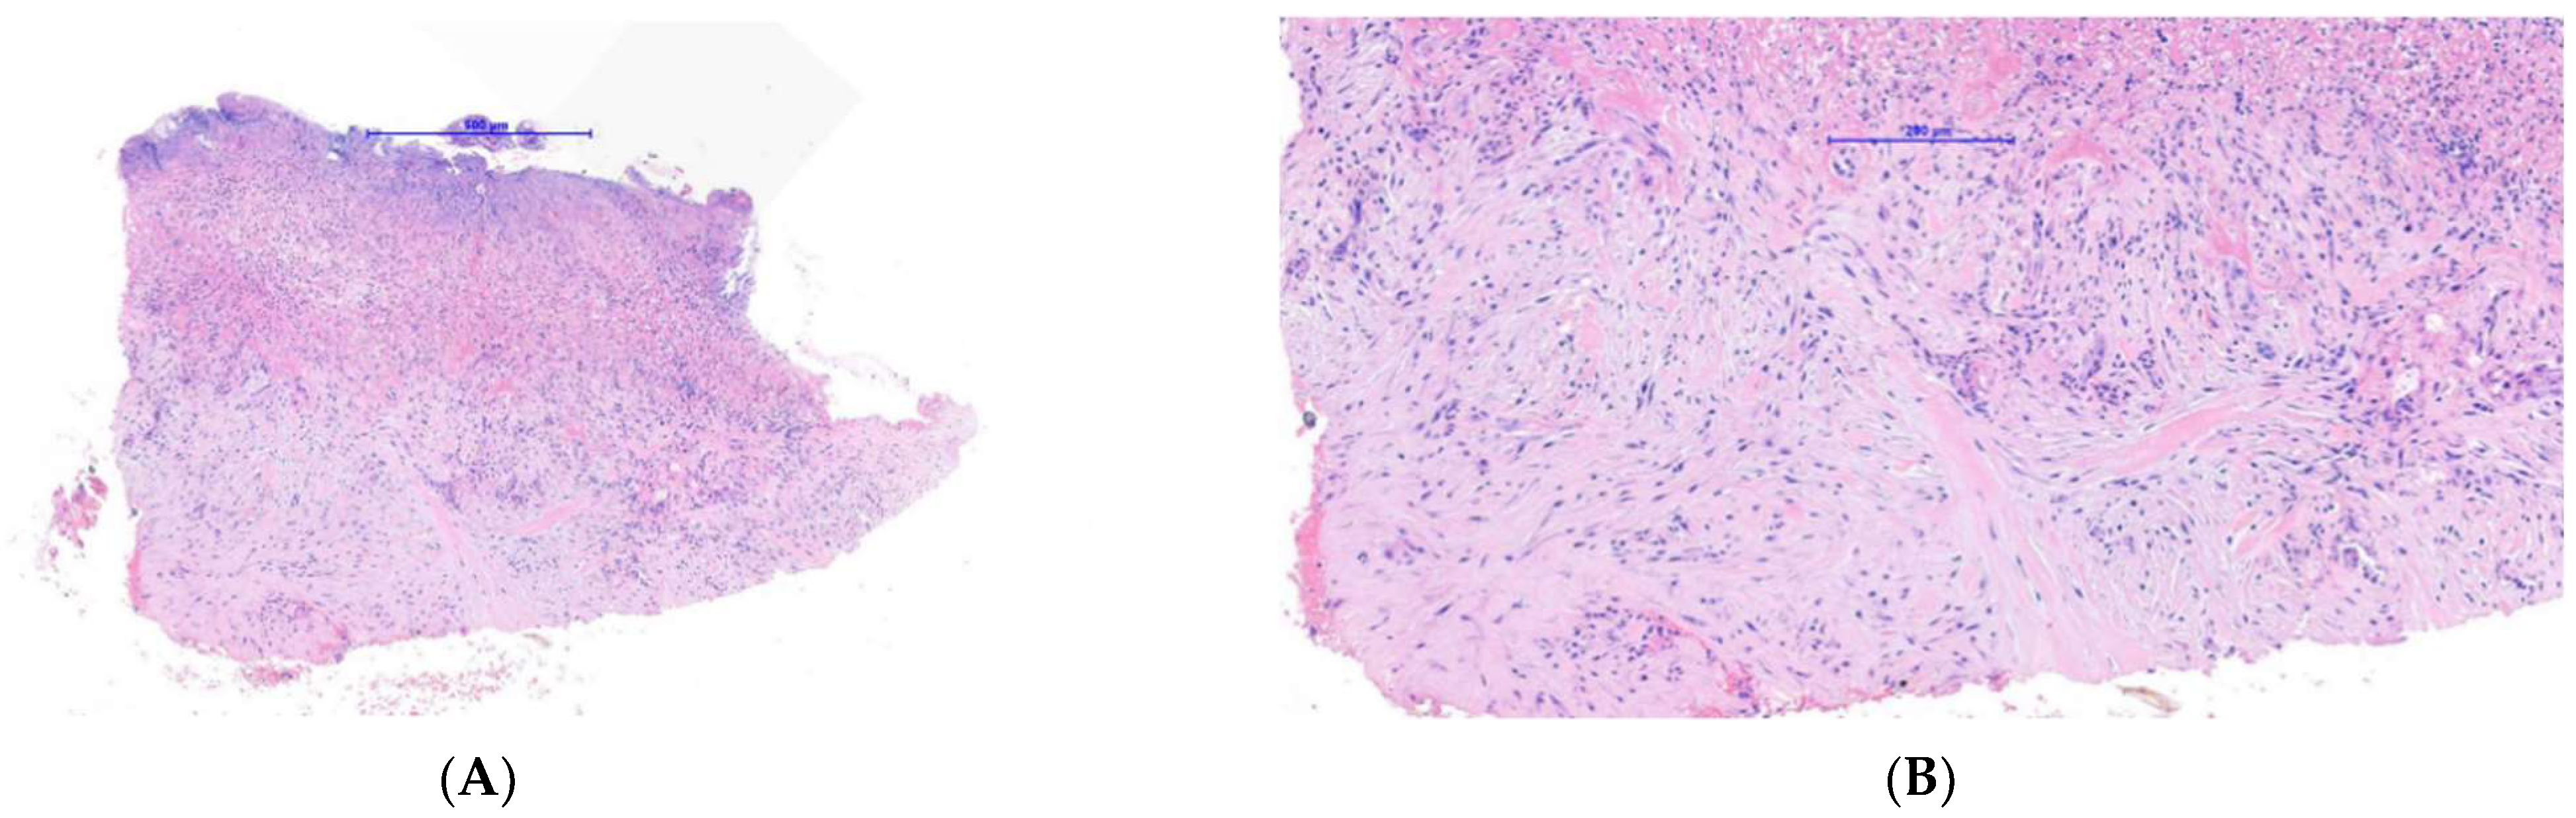

Case 2: A 20-year-old female long-distance runner presented with a five-week history of a lesion over the dorsal aspect of her right big toe. She was a university athletic scholar and reported wearing tight fitting spike running shoes to train. She was originally seen by another dermatologist who was concerned about a subungual amelanotic melanoma and referred the patient for biopsy to our department. On examination, there was a subungual erythematous nodule covering the majority of the right big toenail bed (Figure 4). Because of our previous experience with Case 1, a SE was suspected at the same time a diagnostic biopsy was being performed to exclude amelanotic melanoma. As a result, a plain X-ray showed an exostosis of the distal phalanx and histology showed ulcerated tissue with an underlying myofibroblastic proliferation associated with myxoid stroma and focal keloidal-like collagen (Figure 5A–C). Of note, this sample was relatively superficial and, therefore, did not show underlying cartilage and bone. Immunohistochemistry showed that the lesional spindle cells were strongly and diffusely positive for SMA (Figure 5D) and negative for keratin and melanocytic markers. As with the first case, this suggested a reactive myofibroblastic proliferation secondary to the underlying exostosis. The patient decided not to proceed with surgery given her concerns regarding this impacting her athletic training and performance.

Figure 5. Histopathology of case 2: (A) Low power image showing an ulcerated spindle cell proliferation. (B) Medium power image showing spindle cell proliferation associated with myxoid stroma and focal keloidal-like collagen. (C) High power image of spindle cell proliferation demonstrating a myofibroblastic morphology and highlighting focal areas of red cell extravasation and hemosiderin deposition. (D) Immunohistochemistry for SMA, showing strong and diffuse positivity of the spindle cell proliferation in keeping with a myofibroblastic phenotype.